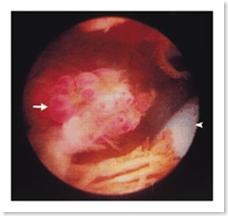

Gambar 6. Artroskopi menunjukkan suatu pedunkulasi, lesi mirip anggur muncul dari sinovial pada lateral parapatella (arrowhead) (MacDonald, et al., 1999).

3. Osseus hemangioma